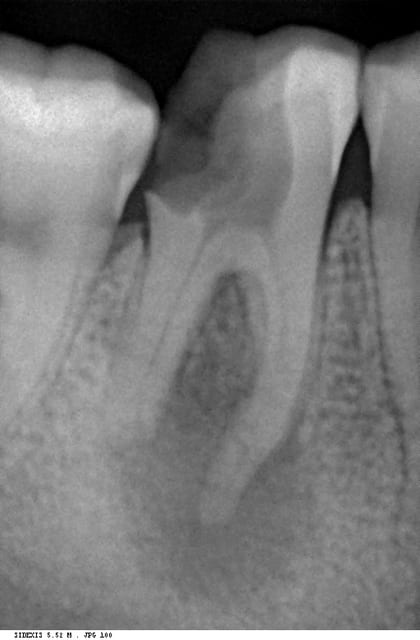

Sans examen clinique compléemntaire, vous ne pouvez pas dire que vous ne la conserveriez pas. En plus cette radio ne semble pas avoir été prise avec un angulateur.

comment évaluer son épaisseur (j'ai vu une couleur sombre entre les deux racines vestibulaires on dirait une couche trés fine de dentine )

Ensuite, tu fais 1 sondage paro :

- atteinte furcatoire ou pas ?

- Si pas d'atteinte, et nécessité d'1 élongation coronaire, tu prends ta radio (avec un angulateur, comme ça tu n'as pas de projection), tu enlèves 2 mm d'os environ et tu regardes à quel niveau tu te retrouves...

Ceci n'a rien de provocateur, mais permet d'insister sur le fait que la seule radiographie ne permet pas de décider quoique ce soit sur ce type de dent ; surtout quand elle n'est pas faite dans les conditions optimales.

Sur la radio on voit qu'il n'y a quasiment plus de plancher: si je veux bien admettre qu'une mauvaise angulation puisse faire croire qu'il y a plus de plancher qu'en réalité, je vois mal comment le contraire serait possible.